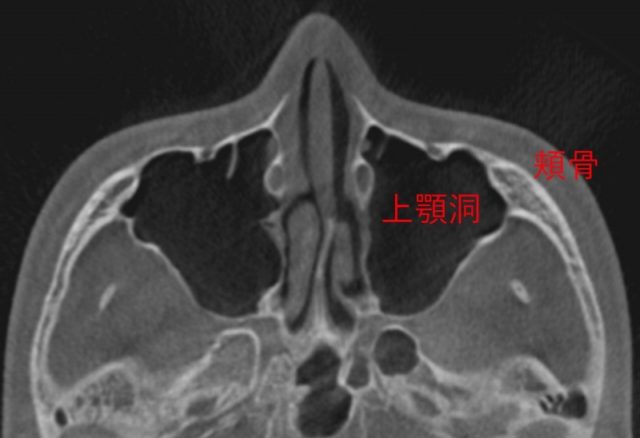

頬骨_痛い時_頬骨と上顎洞

CT像は、こうなります。

頬骨の裏には、

上顎洞という空洞(副鼻腔)があります。

頬骨が痛い事は、

上顎洞炎(副鼻腔炎)と、

関係が近いと言えます。